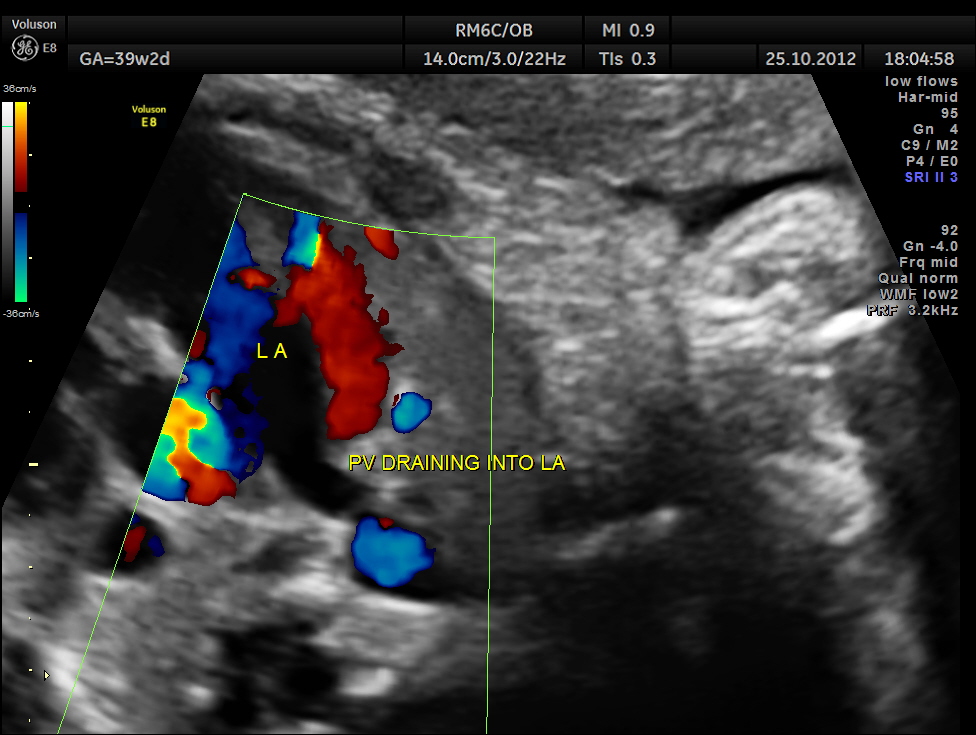

THIS FETUS HAD SEVERE FETAL ANEMIA WITH CARDIAC FAILURE LEADING TO CARDIOMEGALY WITH MITRAL, TRICUSPID AND PULMONARY REGURGITATION .NO OTHER OBVIOUS CARDIAC ANOMALY WAS MADE OUT . THE VENO ATRIAL , ATRIO VENTRICULAR AND VENTRICULO ARTERIAL CONCORDANCE APPEARED TO BE NORMAL; NO SEPTAL DEFECT WAS MADE OUT.